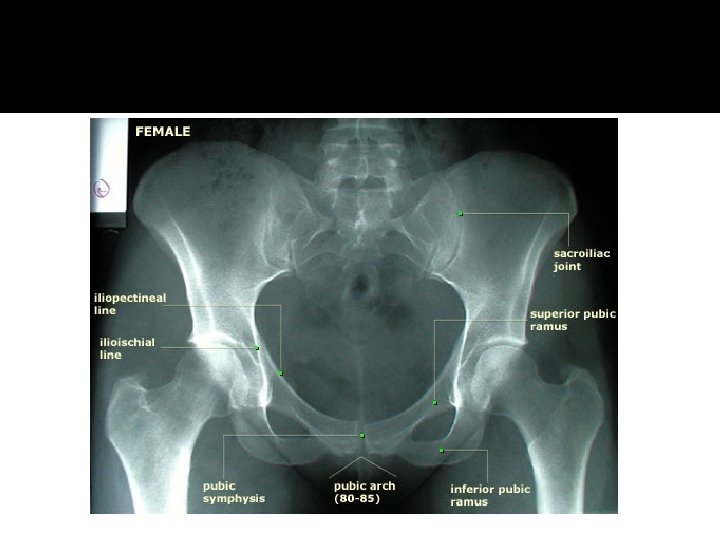

Imaging �AP pelvis can identify 90% of pelvic injuries It can guide the surgeon to additional imaging needs, such as CT scan �AP pelvis during early phase of resuscitation is useful to determine presence or absence of unstable pelvic fracture

Inlet and Outlet Views �Inlet View 45 degree caudal tilt True AP projection of the pelvic brim Evaluates for posterior displacement Evaluates for rotation of ilium and sacral impaction injuries

Inlet and Outlet Views �Outlet View 45 degree cephalad tilt Evaluates for vertical shift of pelvis Visualizes Sacral foramen